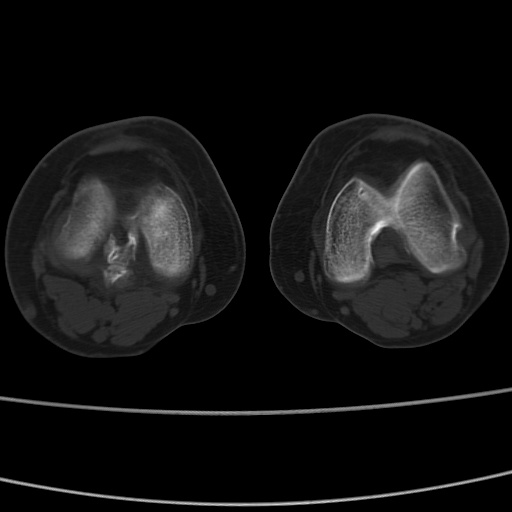

女性,50岁。【请提供患者临床症状体征】

胫骨后缘陈旧性骨折(是否有病史)

右膝关节退行性改变,关节游离鼠。

右膝关节退行性改变,滑膜黏液囊钙/骨化并游离。